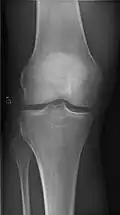

- Knee - AP and Lateral. Intra Condular projections on request

-

Right knee, anteroposterior -

Right knee, lateral -

Patella, (slightly skew) skyline